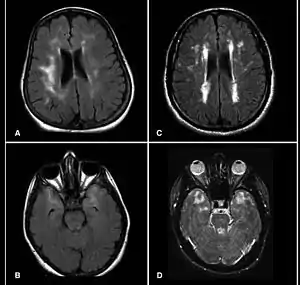

| تصویر امآرآی مغزی در مبتلایان به کاداسیل که چندین ضایعه را نشان میدهد. | |

این بیماری متعلق به گروهی از اختلالات موسوم به لکودیستروفی است و شایعترین علائمش، سردردهای میگرنی و حملات ایسکمیک گذرا (TIA) یا سکته مغزی است که معمولاً در سنین ۴۰ تا ۵۰ سالگی خود را نشان میدهد. تصویربرداری امآرآی قادر است نشانههای این بیماری را، سالها پیش از پدیدار شدن تظاهرات بالینیاش تشخیص دهد.[2][3]

با آنکه اصولاً امآرآی جهت تشخیص این بیماری بکار نمیرود، اما تغییرات مغزی را بهخوبی نشان میدهد. ضایعات متعدد مغز در اندازههای مختلف بهویژه در اطراف عقدههای قاعدهای، پل مغز و ماده سفید از مشخصههای مهم کاداسل است.